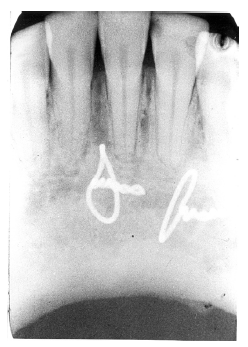

Invagination (Dens in Dente)

Invagination represents a deep infolding of the tooth with extension of the enamel down through the dentin into the pulp. Such teeth can be severely deformed, appearing with an enlarged pulp chamber that has been likened to a tooth within a tooth (dens in dente).

The most commonly affected tooth is the permanent maxillary lateral incisor (Figure 34 and Figure 35). Single dens in dente are most common, but double varieties also occur.

Figure 34 - Invagination

Figure 34

Figure 35 - Invagination

Figure 35